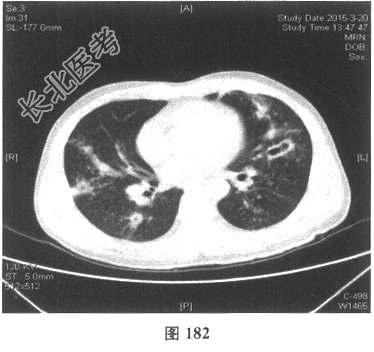

- [材料题] 患者男性,52岁,因间断发热伴咳嗽,咳少许黄痰,无咯血,伴胸闷憋气20余天就诊。体检:体温37.6~38.3℃。既往体健。查体:体温37.6℃,心率83次/分,呼吸20次/分,血压117/64mmHg。神志清,精神可,口唇无发绀;双肺呼吸音粗,可闻及广泛干、湿性啰音,以干啰音为主;心率83次/分,律齐,各瓣膜听诊区未闻及病理性杂音;腹软,无压痛及反跳痛,肠鸣音3次/分,双下肢无水肿。血常规检查:白细胞计数26.32×109/L,中性粒细胞0.846,血红蛋白117g/L,血小板计数1911×109/L;C反应蛋白119.05mg/L。尿常规检查:隐血2(+),蛋白1(+)。痰培养:曲霉菌属,请排除污染。生化全套检查:白蛋白19.6g/L,谷丙转氨酶24.2U/L,谷草转氨酶25.8U/L,γ-谷氨酰基转移酶91.4U/L;尿素氮13.00mmol/L(2.14~7.14mmol/L),肌酐166.8μmol/L(31~132μmol/L);血钾5.6mmol/L。肺部CT见图178~图185。

C、肺部CT常见肺内多发团块状影,常见空洞